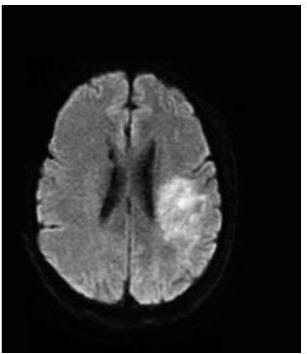

• 肿瘤样脱髓鞘病变报道3例

2023, 48(5):614-617. DOI: 10.13406/j.cnki.cyxb.003183

摘要 (95) HTML (24) PDF 1.29 M (241) 评论 (0) 收藏

摘要: